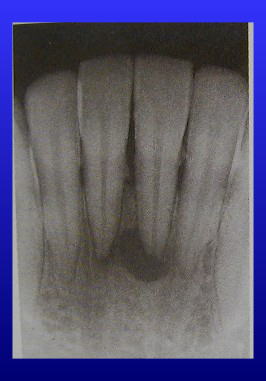

レントゲン写真で見ると、歯の中の黒い筋状の部分が神経の入っている管です。

(写真では根の先端にウミのフクロが黒く写っています)